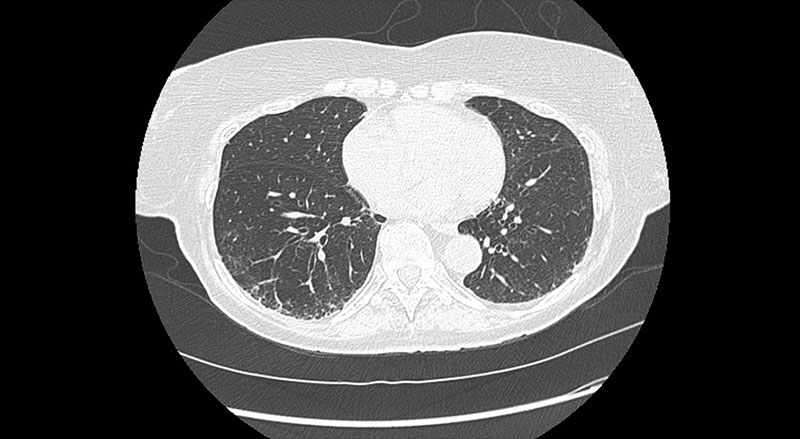

CT image showing ILA with early signs of fibrosis identified through lung cancer screening